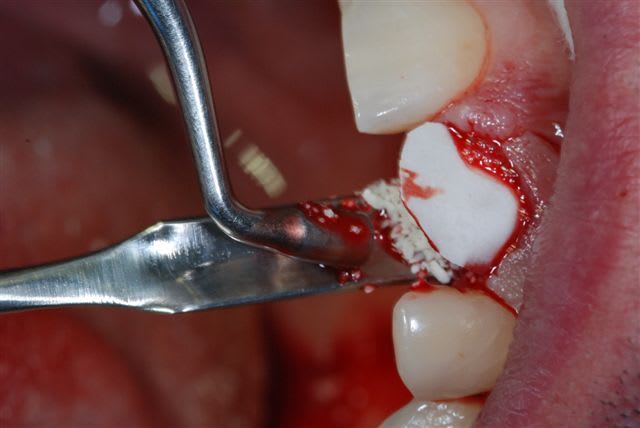

j'ai eu un cas ce matin tout indiqué pour cette technique, racine de 21 fracturée il y a 3 ans lors d'une intubation. j'ai découpé une biomend extend 15x20 en cône (maintenant zimmer commercialise des membranes déjà découpées).

Decoupe h88qev - Eugenol

Membrane en place a3qcfe - Eugenol

Gen os e7lxa9 - Eugenol